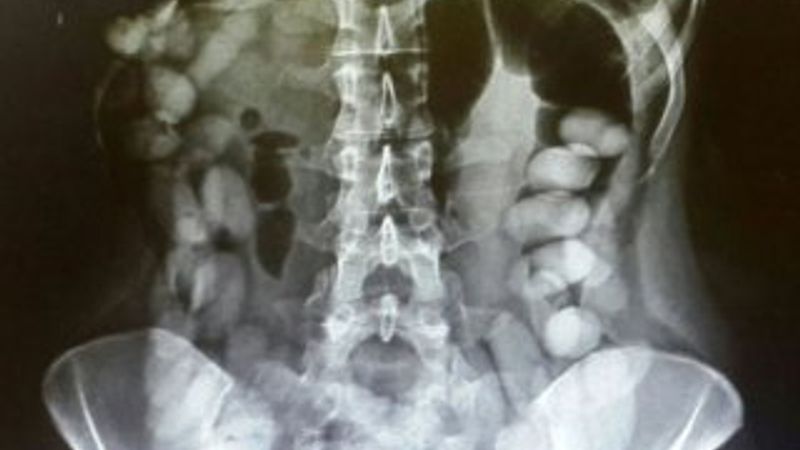

Tayland basınındaki haberlere göre, gümrük memurları x-ray cihazından geçen Suamu Nkele'nin midesinde bazı maddeler göründüğünü tespit etti.

İncelemeler sonrası midesinde 1,2 kilogram uyuşturucu madde bulunan kadının çorap ve iç çamaşırlarına da uyuşturucu yerleştirdiği ortaya çıktı. Angola'nın başkenti Luanda'dan Bangkok'a seyahat eden kadın, emniyet güçlerince gözaltına alındı.